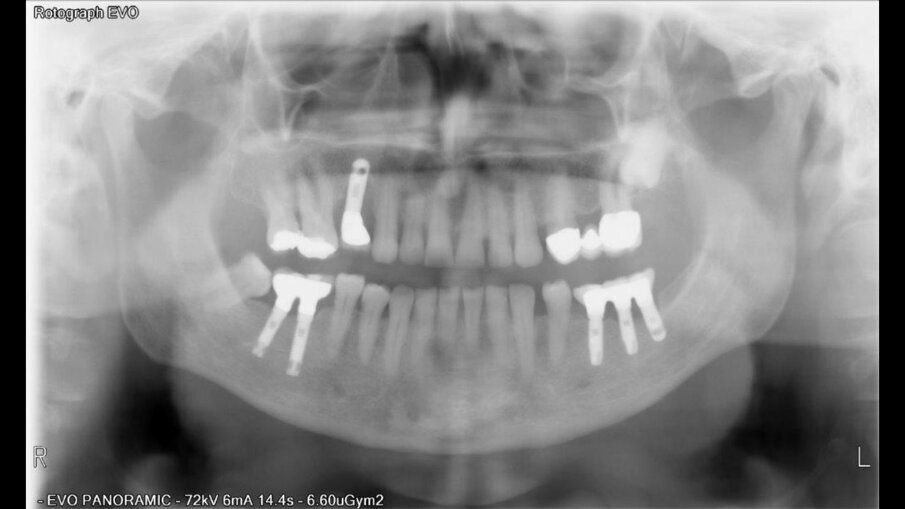

Posuzovali jsme 181 pacientů (97 žen a 121 mužů s průměrným věkem 49,2 let) se 721 implantáty. Z toho bylo zavedeno 384 implantátů na úrovni kosti, 289 zúžených implantátů na úrovni kosti a 48 implantátů na úrovni měkkých tkání (tabulka 2). Implantáty byly klasifikovány podle jejich pozice v horní a dolní čelisti. Pokud jde o anamnézu kouření u pacientů, počet denně vykouřených cigaret se pohyboval mezi 20 a 60 cigaretami.

Po chirurgickém zákroku byly pořízeny periapikální RTG snímky, na nichž byla zkontrolována přesnost zavedení implantátů. Pooperační medikace spočívala v předepsání antibiotik. Digitální RTG snímky byly pořízeny v době chirurgického zákroku, po 24 hodinách a jeden měsíc po zákroku, a to za účelem vyhodnocení úspěšnosti implantologického ošetření. Zánětlivé procesy byly zjištěny u 24,1 % pacientů. V případě potřeby byla provedena augmentace za použití materiálu NanoBone (Artoss), kostní náhražky Geistlich Bio­Oss a membrán Geistlich Bio-Gide (oba produkty Geistlich Biomaterials).

Ze 721 implantátů selhalo celkem 65 implantátů. Míra úspěšnosti tedy ve výsledku byla 90,98 %, tedy nižší než v naší předchozí studii provedené u nekuřáků, u nichž byla míra úspěšnosti 98,70 %.2 U skupiny neúspěšných implantátů selhala většina z nich (74,5 %) dva až čtyři týdny po zavedení v důsledku nedostatečné oseointegrace. Periimplantitida se vyskytovala u 20 % neúspěšných implantátů. To lze přičíst špatné ústní hygieně a tvorbě plaku. U 4,6 % případů se periimplantitida objevila v rozmezí jednoho až tří let po zavedení implantátu v důsledku mechanických problémů po úbytku kosti. Nebyla zjištěna žádná souvislost mezi délkou a průměrem implantátu a mírou selhání, ani mezi počtem vykouřených cigaret a mírou selhání implantátu.